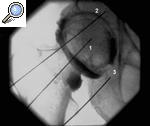

Figura 3. Bloqueo del nervio supraescapular con control radiológico. Nótese la varilla (1) marcando la fosa supraescapular (2).

La aguja se introduce perpendicularmente hasta que se localiza el nervio o se llega a tocar el hueso en la fosa supraescapular (fig. 3). Si sucede esto, se debe dirigir la punta de la aguja ligeramente hacia medial hasta que se localice el nervio.